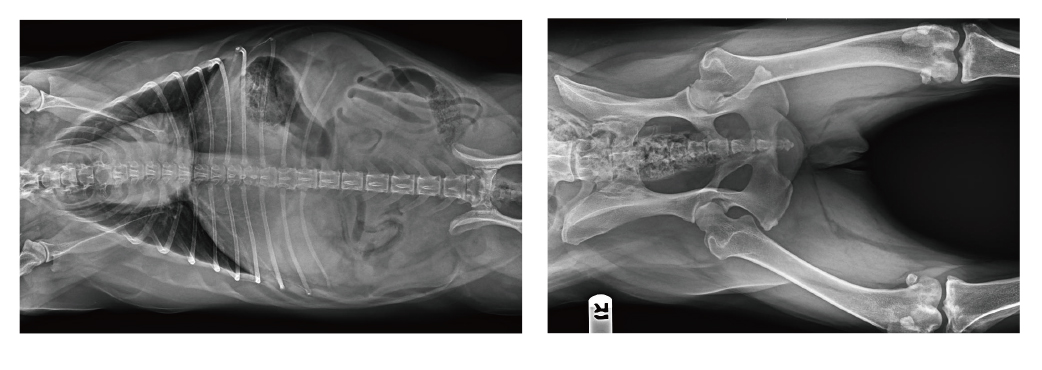

【寵物x射線機臨床圖像】